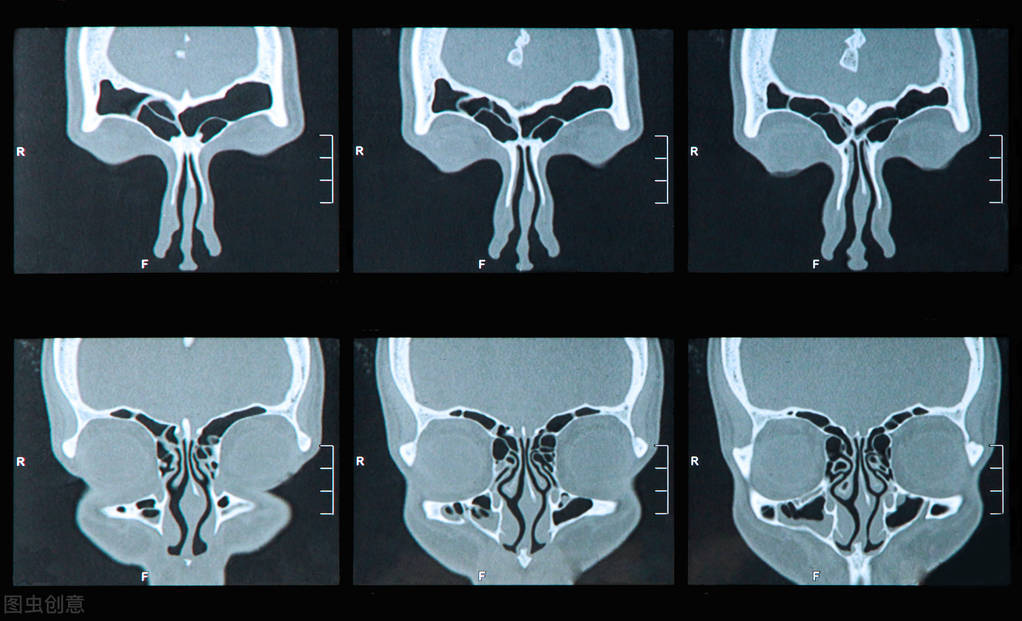

- 鼻窦CT检查,是确诊鼻窦癌症的“金标准”,能观察出肿瘤的大小、侵犯范围和边界的情况;